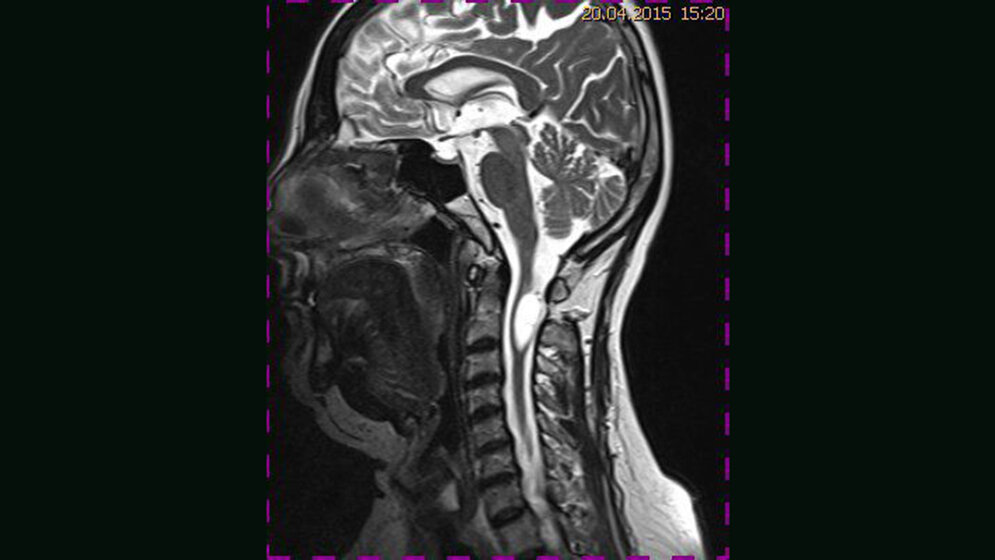

Tumoröse Veränderungen: Medulläres Hämangioblastom

Hämangioblastome sind gutartige Tumoren, die sporadisch oder im Zusammenhang mit dem M. Hippel-Lindau auftreten können. Die genetische Veränderung der Zellen intraduraler Tumoren kann einen entscheidenden Einfl uss auf die Therapieoptionen und die Prognose für die Patienten haben. Die Kombination von vaskulären Anomalien mit Gliomen ist im zentralen Nervensystem sehr selten. Hämangio-blastome können Ursache einer intramedullären Blutung sein.